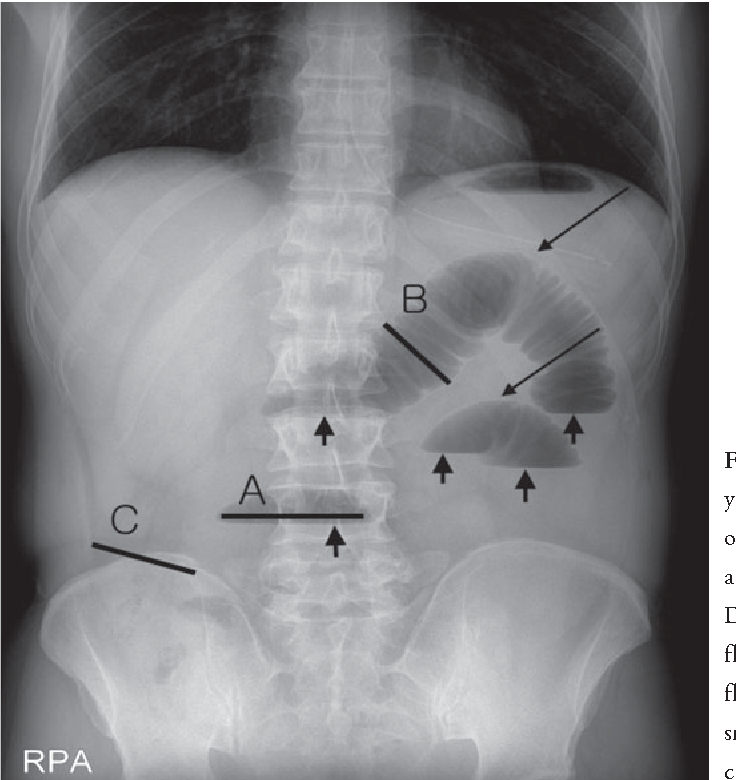

Q.11. Initial investigation in small bowel obstruction is?

Correct Answer : A

Erect abdominal X-ray because it shows air-fluid levels, a key sign of small bowel obstruction. It's quick, simple, and effective for initial diagnosis.

Incorrect options-

- CT scan is more detailed but not the first line test.

- MRI is too complex and costly.

- Colonoscopy is irrelevant for diagnosing small bowel obstruction.